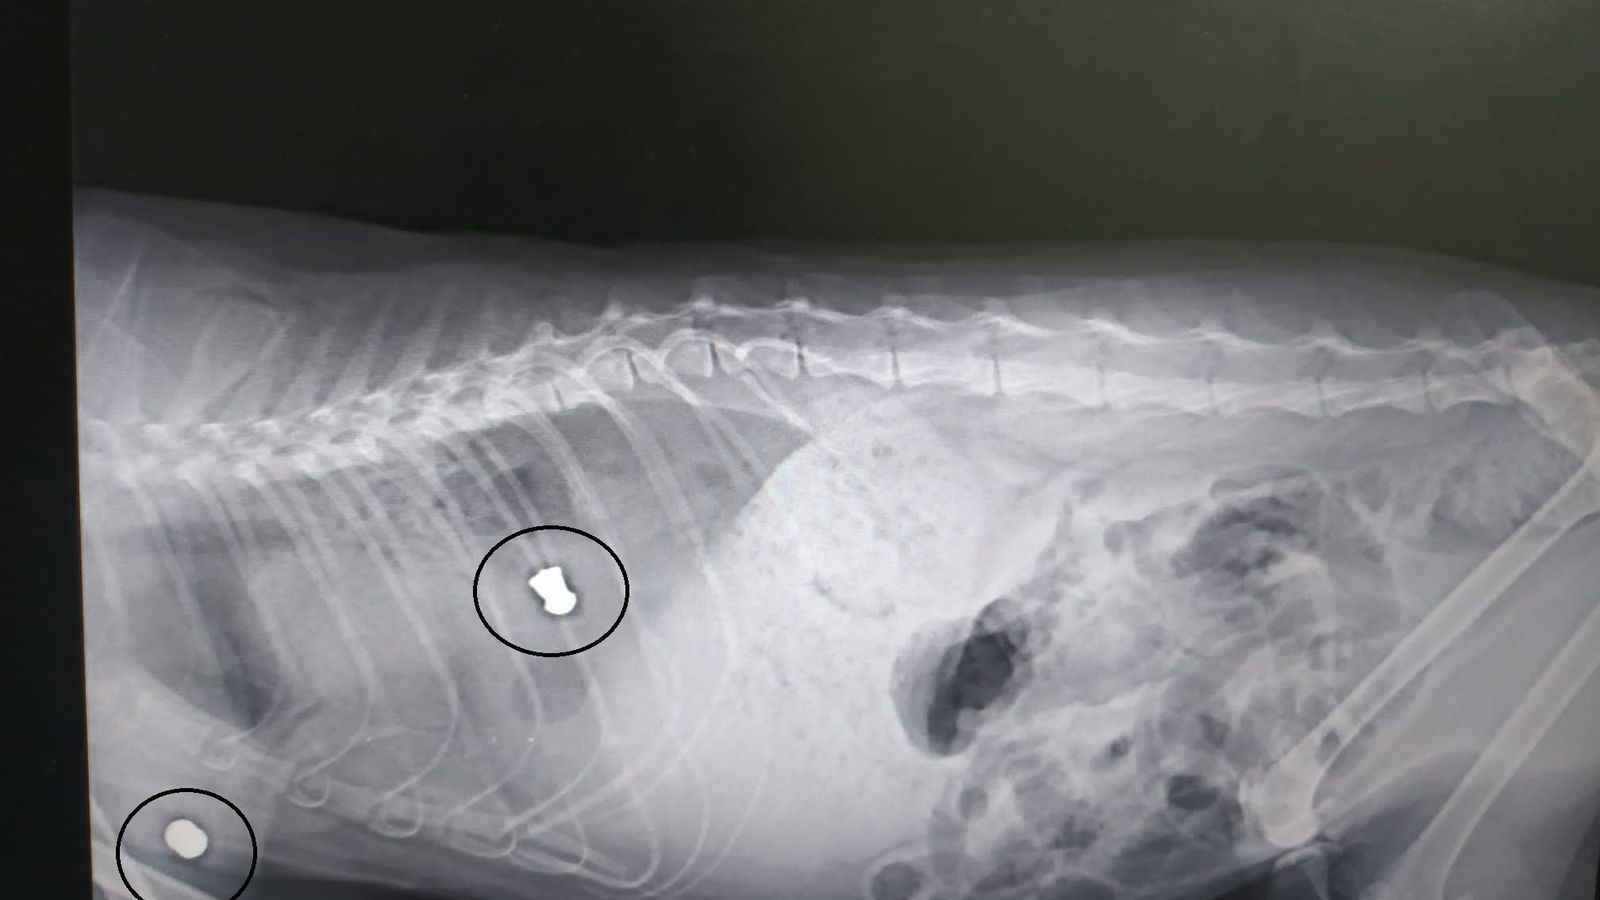

-Disparan a los gatos causándoles una dolorosa muerte. Las radiografías demuestran los órganos afectados, como ha sido casos en la columna vertebral o en el tórax.

Radiografía en la que se aprecian dos balazos en el cuerpo de un gato